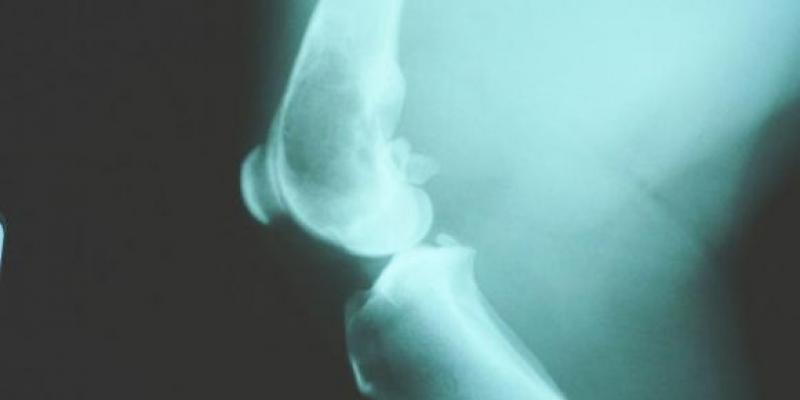

El osteosarcoma es el cáncer de huesos más común en niños. También llamado sarcoma osteogénico, se trata de un tumor derivado de las células que generan el hueso.

Además, este tipo de cáncer tiende a ocurrir en los huesos más grandes del cuerpo como la espinilla, el muslo o el brazo, donde el crecimiento óseo es más rápido. Pese a ello, puede comenzar a su crecimiento en cualquier otro hueso, extendiéndose después al resto. A veces también se propaga (o hace metástasis) a otras partes del cuerpo, generalmente, los pulmones.